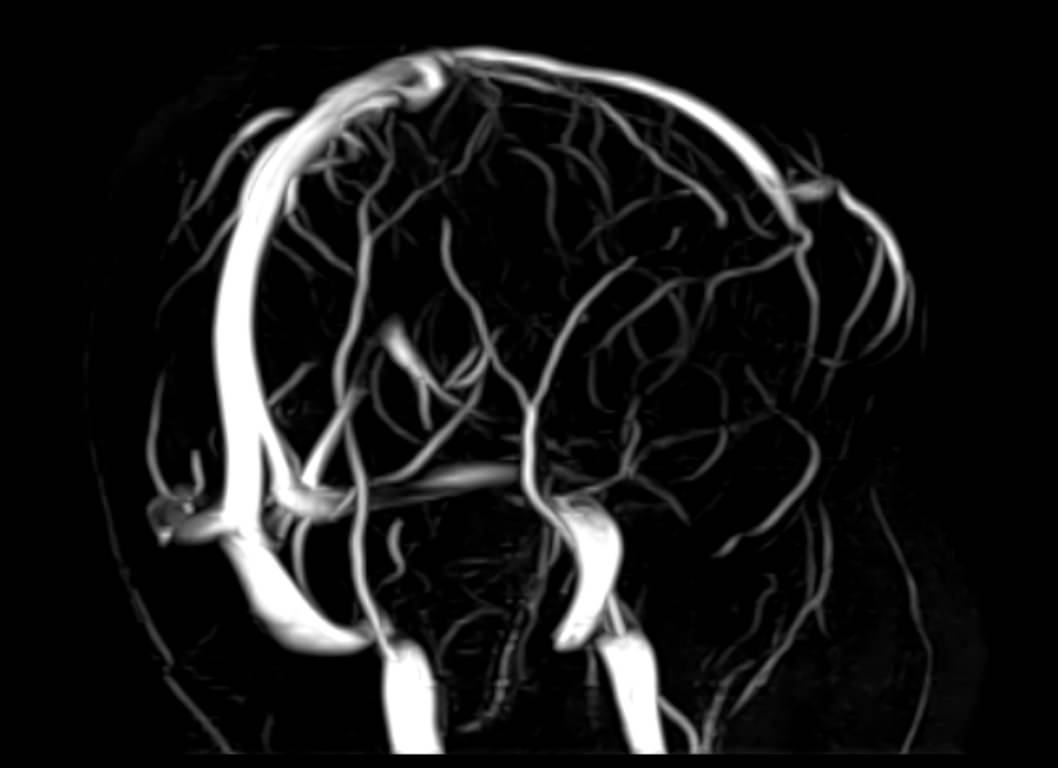

Исследования выполняются на современном высокопольном томографе экспертного класса TOSHIBA VANTAGE TITAN 1,5 Тесла, который использует разные режимы сканирования с толщиной среза от 1мм в различных плоскостях с последующей цифровой обработкой полученных данных для создания трехмерных изображений. МР-ангиография отображает состояние артериальной системы кровоснабжения головного мозга. МР-венография головного мозга позволяет детально изучить особенности венозного русла головного мозга.

Компьютерная программа обрабатывает данные, полученные при сканировании, и формирует объемные изображения как самого мозга, так и сосудистой системы в отдельности без прилегающих тканей. Методики применяются одновременно и взаимодополняют друг друга.